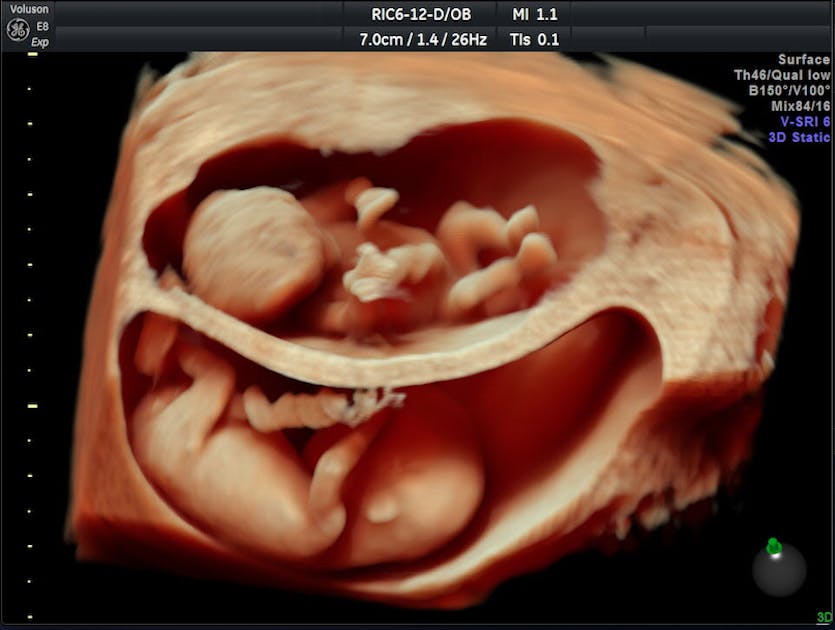

. Binge watch my pregnancy videos 14 weeks sonogram httpsyoutube9_BsxFVS-r016 weeks. At 14 weeks we are able to predict gender at Reveal 3D4D Ultrasound. The ultrasound image is of twins at 4 weeks.

Baby development at 14 weeks Making faces. Ad Free ultrasound images of all stages of fetal development. Crown-rump length or CRL is the measurement used at 14 weeks.

Hes well-developed on the outside but complex changes are taking place as your babys. Ad Kaiser Permanente Has Resources for Parents Taking Care of Their Newborn Children. One development youll have no problem seeing during an ultrasound at this.

14 Weeks Pregnant With Twins Ultrasound Symptoms And More Twinstuff